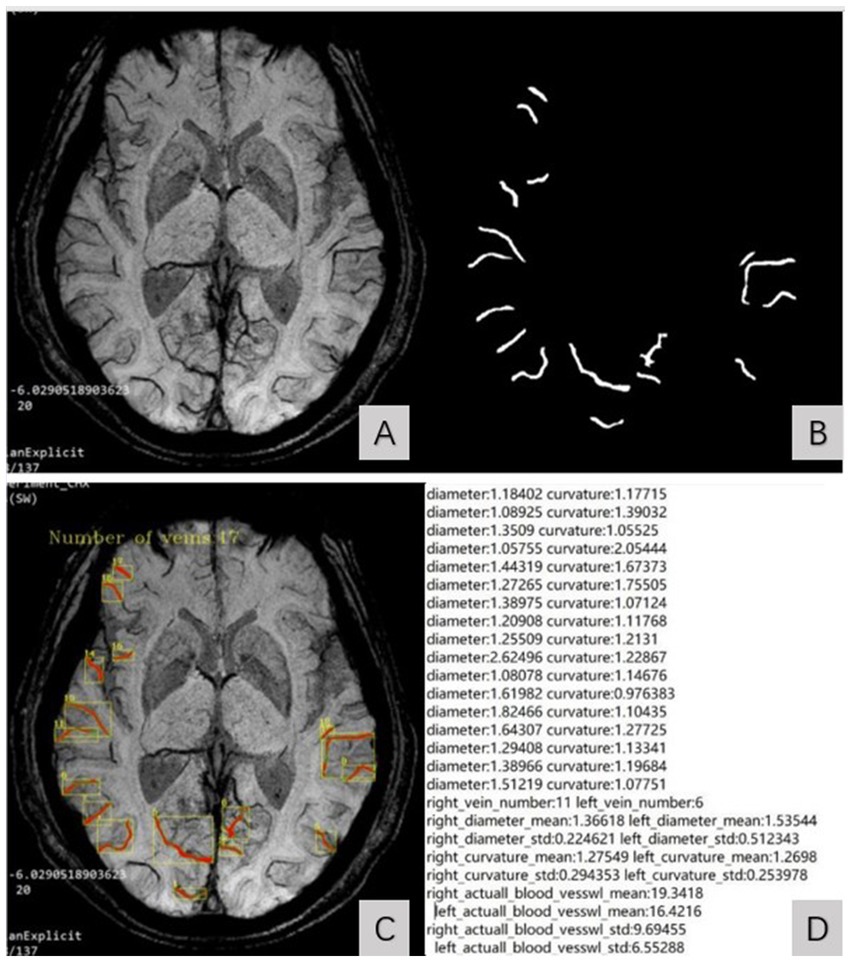

By inputting MinIP JPG images of all slices of the subject’s bilateral cerebral hemispheres into the model, the diameter, curvature, length, and number of SCVs in the bilateral cerebral hemisphere can be automatically identified and quantified. The output parameters include the diameter, curvature, length and number of SCVs displayed on the detection slice. The curvature of the SCV was defined as the ratio of the length of the venous vascular curve to the linear distance between two points on either end, indicating the tortuous degree of the SCV. The SCV quantification data of all slices in the bilateral cerebral hemispheres of each subject were automatically organized into an Excel table for statistical analysis. The process of the image segmentation algorithm model recognizing the SCV is shown in Figure 1.

Figure 1

SCV image segmentation and recognition steps. (A) showed the original MinIP image. (B) showed the identified SCV of bilateral cerebral hemispheres. The identified SCVs were automatically superimposed on the original MinIP image (C) and generate the quantized value of the SCV at the detection slice (D).